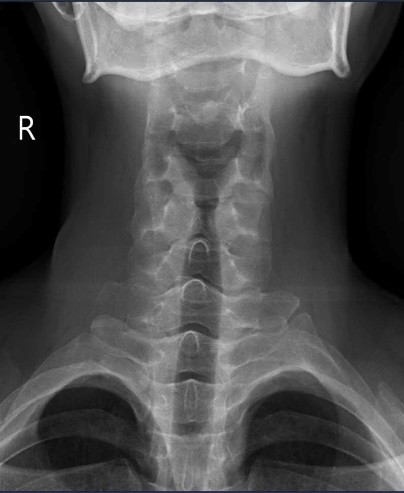

Tại Khoa Khám chữa bệnh theo yêu cầu và quốc tế, Bệnh viện E, ThS.BSNT Nguyễn Mạnh Quyết nhận thấy đây là trường hợp đau cột sống kiểu viêm – dấu hiệu then chốt gợi ý bệnh lý viêm khớp mạn tính. Bệnh nhân được chỉ định chụp X-quang khớp cùng chậu và làm xét nghiệm gen HLA-B27.

Kết quả cho thấy, bệnh nhân bị viêm khớp cùng chậu độ III hai bên, HLA-B27 dương tính, CRP và tốc độ lắng máu tăng. Trong khi đó, X-quang cột sống cổ vẫn chưa có biểu hiện dính khớp hay gai xương.

Theo ThS.BSNT Nguyễn Mạnh Quyết, viêm cột sống dính khớp là bệnh viêm mạn tính, thường gặp ở nam giới trẻ dưới 45 tuổi. Giai đoạn đầu, tổn thương X-quang cột sống có thể chưa rõ, trong khi khớp cùng chậu lại là vị trí bị ảnh hưởng sớm nhất.